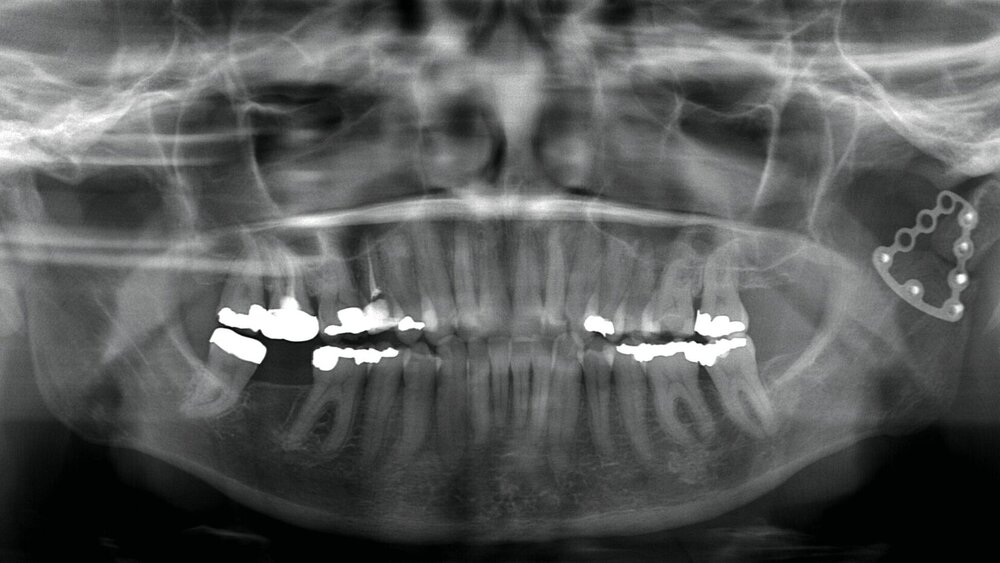

Anamnestisch waren bei ihr im März 2021 eine beidseitige Collumfraktur mit begleitendem frontoffenem Biss und eine Corpusfraktur im Unterkiefer infolge eines synkopalen Sturzes nach einer COVID-19-Impfung aufgetreten. Da das linke Collum in Fehlstellung verheilte, erfolgte alio loco eine operative Revision mit Osteosynthese (Abbildung 1). Das Metall wurde im April 2022 entfernt. Der Hauszahnarzt führte daraufhin im Verlauf eine Aligner-Therapie durch, um die immer noch fehlerhafte Okklusion zu optimieren sowie diverse Dreh- und Kippstände zu beseitigen.

Im Rahmen der Konsultation der Mund-, Kiefer- und Gesichtschirurgie und der Kieferorthopädie erfolgte eine erneute radiologische Bildgebung (Abbildung 4). Die Patientin wurde im Anschluss beraten, dass eine Re-Osteotomie des ehemals frakturierten und nun in Fehlstellung verheilten Collumsegments links ihr Okklusionsproblem adäquat lösen könnte. Ebenso sei eine orthognathe Umstellungsosteotomie möglich. Nach ausführlicher Aufklärung entschied sich die Patientin allerdings gegen eine chirurgisch-kieferorthopädische und für eine rein prothetische Lösung. Die Patientin hatte derart Angst vor einem erneuten chirurgischen Eingriff, dass sie selbst die Aussicht auf eine längere und invasivere prothetische Behandlungsphase nicht abschreckte.